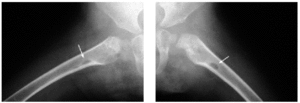

En el estudio complementario realizado que incluyó analítica completa, pruebas inmunológicas, niveles de aminoácidos y de mucopolisacáridos y pruebas serológicas para sífilis, citomegalovirus, toxoplasma y rubéola fueron normales. El cariotipo también fue normal y en el estudio radiológico se revelaron quistes osteolíticos en la parte proximal de ambos fémures y múltiples contracturas en flexión de las articulaciones con un aumento de la densidad de partes blandas periarticulares que les hacía radiológicamente visibles (figs. 3 y 4). El estudio histopatológico de una lesión tumoral puso de manifiesto una importante papilomatosis con una dermis papilar engrosada y una matriz eosinofílica hialina PAS+ sobre las que existen células de hábito fibroblástico (figs. 5 y 6). Existe una ausencia de tinción para fibras elásticas y un leve infiltrado inflamatorio linfocitario rodeando a algunos ductus.

Fig. 4.--Estudio radiológico que muestra quistes osteolíticos en la parte proximal de ambos fémures.

El retraso mental no es frecuente y son pacientes intelectualmente normales13. Las lesiones óseas radiológicas incluyen osteólisis en la parte distal de las falanges y el cráneo16, osteoporosis, erosiones simétricas en la cortical de huesos largos y calcificaciones de los tejidos blandos periarticulares y en la cápsula articular. La talla corta es una característica observada en algunos casos8. El resto de la exploración física es normal.